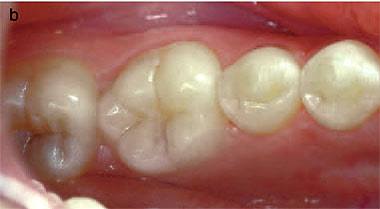

อันนี้คนละเคสนะครับ แสดงออก Class 2 คือ รอยโรคขนาดใหญ่ขึ้นจนฟันเริ่มมี pink discoloration

film ซี่ 11 lesion ซ้อนทับกับ pulp (อยู่ในแนว labio-lingual จึง superimpose กับ pulp แต่ยังไม่ expose pulp ครับ)

ความแปลกของ Invasive cervical resorption คือ มันไม่ค่อยจะ expose pulp ครับ จากรูปของอีกเคสนึง เป็น Class 2 จะเห็นว่า ถ้ารอยโรคอยู่ในตำแหน่ง proximal (ไม่ซ้อนทับ pulp) เราจะสังเกตเห็น radiopaque line บางๆ กั้นระหว่างรอยโรคกับ pulp (แสดงลักษณะของกลไกป้องกันตนเองของฟัน)